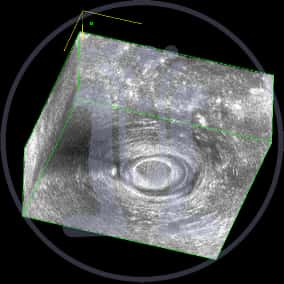

Ο Ι.Π. 85 ετών πατέρας φίλου ιατρού παρουσιάζει τσούξιμο στην περιοχή του πρωκτού. Μετά την τηλεφωνική συνομιλία αποστέλλεται με τηλεφωνικό μήνυμα, φωτογραφία της περιοχής του πρωκτού. Τίθεται η υποψία συριγγίου. Τελικά πείθεται ο ασθενής και προσέρχεται στο ιατρείο. Στο ιστορικό τελικά αναφέρεται ότι προ διμήνου υπήρξε πόνος ο οποίος παρήλθε μετά από εκροή υγρού. Η λεπτομερής κλινική εξέταση δείχνει στόμιο το οποίο και διερευνάται με ειδική μήλη. Το ενδοπρωκτικό υπερηχογράφημα με χρήση σκιαγραφικού αποδεικνύει την ύπαρξη συριγγίου, το οποίο είναι πολύ χαμηλό και δεν παρουσιάζει σημαντικό κίνδυνο.